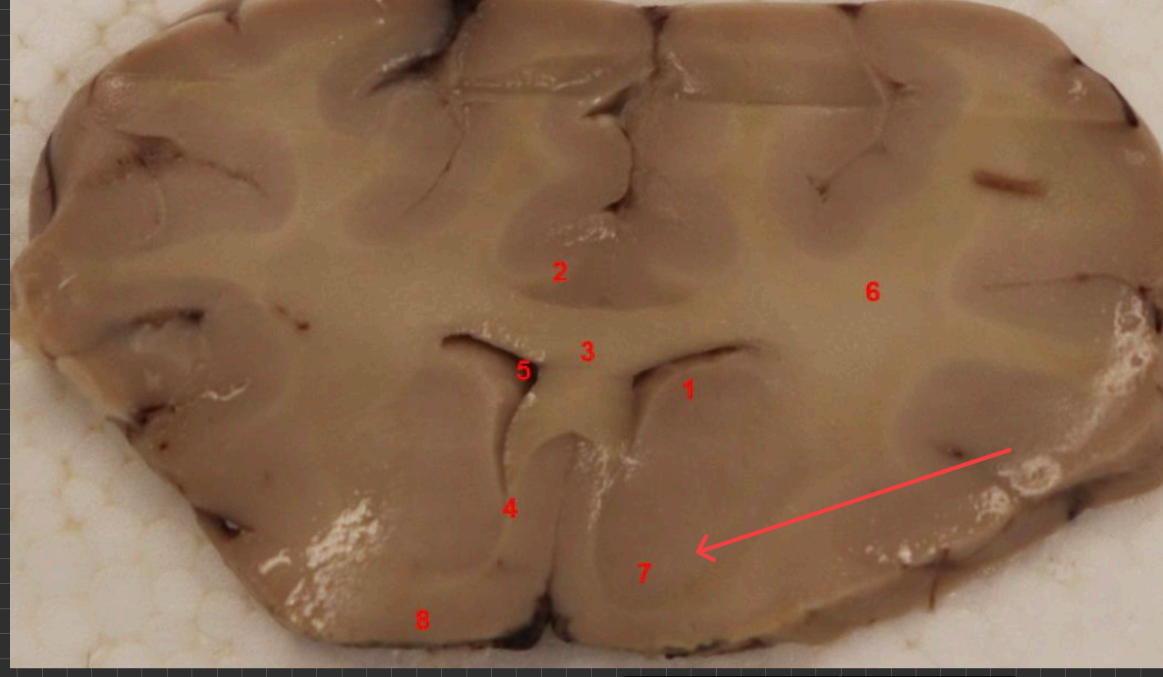

What nuclei is this, function?

Caudate Nucleus , motor control, voluntary movement planning, and procedural learning (habits)

what area is this, function?

nucleus accembus, reward, pleasure, addiction, and motivation.

what tract is this, ?

Cingulum bundle

what COMMISSURE i s this

genu of corpus callosum

what tract is this ? function?

septohypthalmic tract

what ventricle is this

lateral

what area is this

Olfactory Tubercle

what commisure is this

body of corpus callosum

septum pellucidum